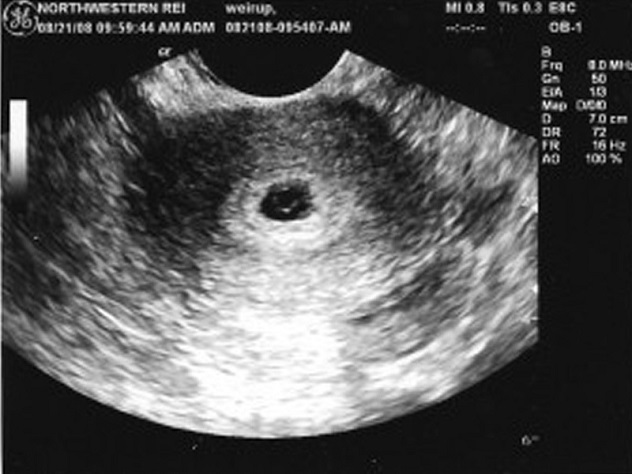

Плодное яйцо в матке — это начальная стадия развития эмбриона, которая формируется после оплодотворения. На ультразвуковом исследовании (УЗИ) плодное яйцо становится видимым примерно на 5-6 неделе беременности. В этот период оно выглядит как небольшое черное образование, окруженное белым контуром, что указывает на наличие жидкости. Эксперты подчеркивают, что раннее обнаружение плодного яйца имеет важное значение для оценки состояния беременности и исключения внематочной беременности. Однако на более ранних сроках, до 5 недель, его визуализация может быть затруднена, и в таких случаях рекомендуется повторное УЗИ через несколько дней для более точной диагностики. Правильная интерпретация результатов УЗИ требует опыта и знаний, поэтому важно доверять квалифицированным специалистам.

Начнем с ультразвукового исследования, поскольку оно считается наиболее точным и результативным. Проведение процедуры поможет не только диагностировать наступление беременности, но и определить размеры плодного яйца, его форму и местоположение.

УЗИ считается самым точным методом диагностики, особенно если оно проводится трансвагинальным методом, с введением датчика во влагалище женщины.

При проведении такого исследования полученных результатов достаточно для того, чтобы выявить патологию беременности, поставить срок, диагностировать наличие или отсутствие беременности у женщины.